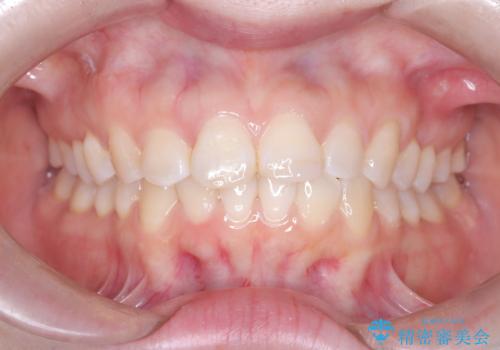

- 前歯のデコボコ(叢生)を気にされてご来院されました。精密な検査の結果、歯が並ぶスペースが不足していることが判明。患者様のご希望から、透明で目立ちにくいインビザライン(マウスピース矯正)による治療計画を立案しました。抜歯を避け、奥歯全体を奥へ動かす遠心移動という方法でスペースを確保し、前歯の叢生を解消することを目指します。

今回の矯正治療では、透明なマウスピース型の装置インビザラインを使用しました。この装置は取り外し可能で、日常生活で目立ちません。治療は、緻密に計算された計画に基づき、段階的に作製されたマウスピースを交換していくことで、奥歯から順に全体を後方へ移動させる遠心移動を実施。これにより、前歯を並べるための十分なスペースが確保され、デコボコが解消されました。抜歯することなく、機能的にも審美的にも整った美しい歯並びを獲得していただけました。